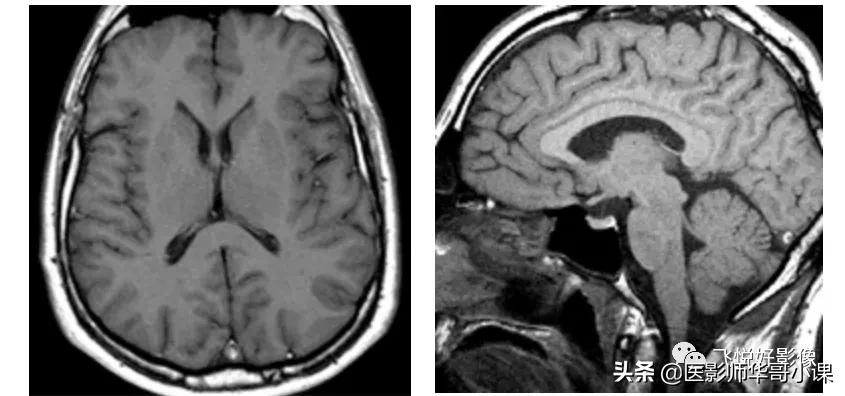

我们通过磁共振脑实质成像,来表现不同加权图像的信号对比特点,通过短TR、短TE实现T1加权成像;通过长TR、长TE实现T2加权成像(由于SE采集效率低,在实现T2加权中,可利用快速自旋回波序列TSE代替);通过长TR、短TE实现PD加权成像。

图2,SE T1加权图像。左图为横断面脑实质T1加权图像,TR=582ms,TE=12ms。右图为矢状面脑实质T1加权图像,TR=480ms,TE=12ms。T1加权图像主要用于显示脑实质解剖结构,脑白质相对于脑灰质显示为稍高信号;脑脊液在T1加权图像中为低信号,皮下脂肪组织、骨髓脂肪组织显示为高信号,而骨结构、空气等在磁共振中不产生信号。(图像源自飞利浦磁共振系统)